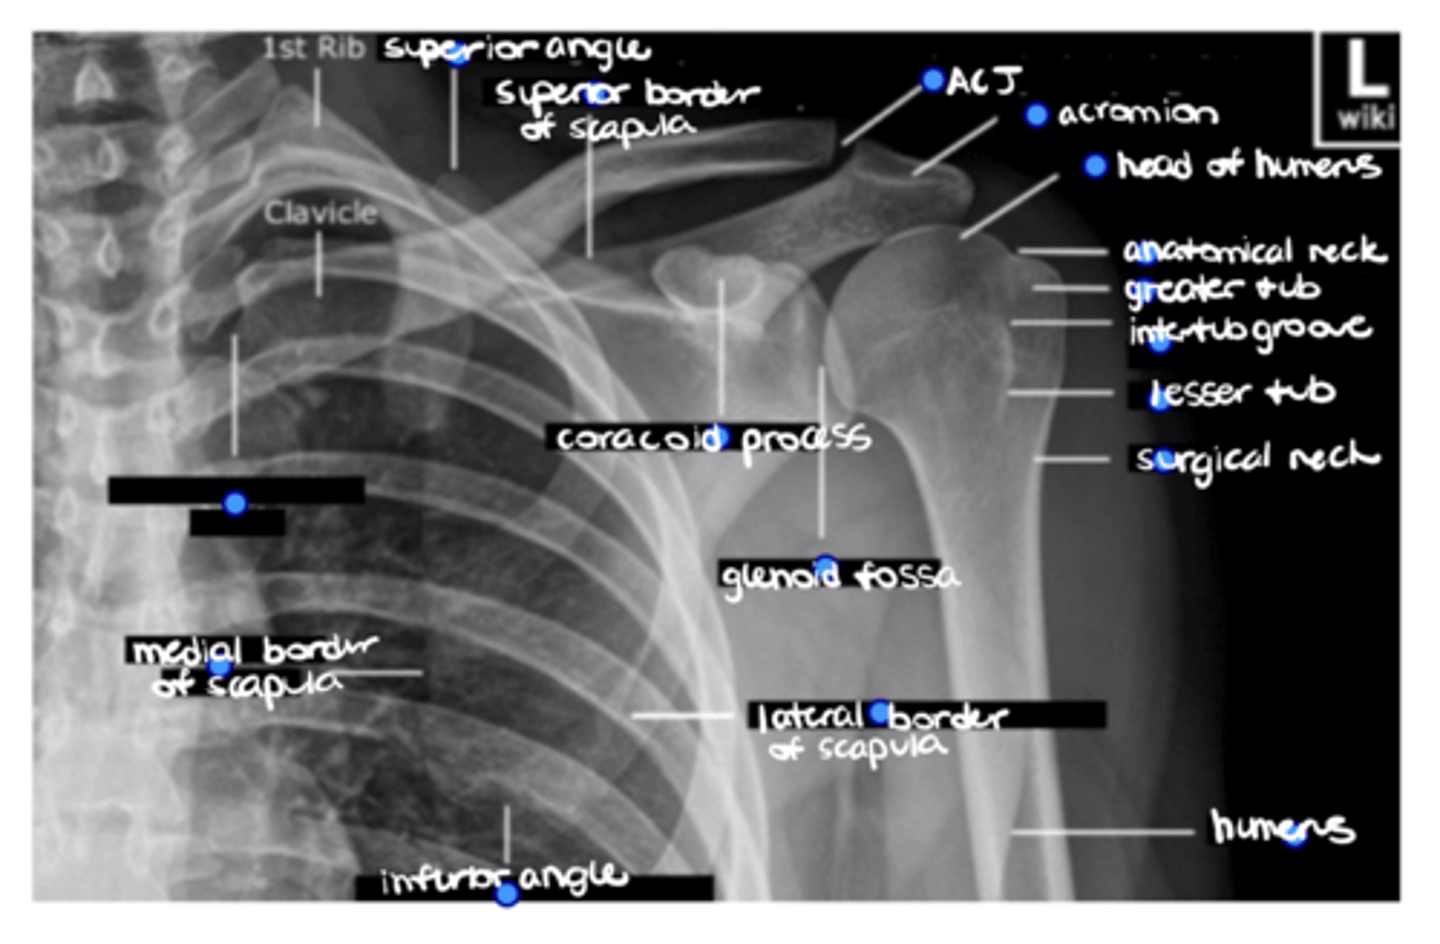

Shoulder trauma, dislocation, and suspected GHJ OA, ACJ OA, or ACJ separation

When is a shoulder x-ray indicated?

AP (frontal/coronal), lateral (sagittal), Y-view/scapular view (allows you to see the orientation of the head of the humerus in the glenoid), and axial (transverse)

NOTE: this picture is an AXIAL view of the shoulder

Which types of x-ray views are common at the shoulder?

TRUE!!--we see healthy space b/w the clavicle and acromion, the humerus and the acromion, and b/w the glenoid and humerus...also, there is no sclerosing or osteophytes

True or false: this is a healthy GHJ

1. Distal clavicle

2. Coracoid

3. Glenoid

4. Head of humerus

5. Lesser tuberosity

6. Greater tuberosity

7. Clavicle

8. AC joint

Label this image.

INTERNAL, because the lesser tuberosity is positioned medially vs. in line with the greater tuberosity, as seen in external rotation

Is this shoulder in EXTERNAL or INTERNAL rotation? Why?

Superior angle of the scapula

ID the missing structure.

Superior border of the scapula

ACJ

Acromion

1. Head of humerus

2. Anatomical neck

3. Greater tuberosity

4. Intertubercular groove

6. Surgical neck

ID the 6 missing structures.

Shaft of the humerus

1. Coracoid process

2. Glenoid fossa

ID the 2 missing structures.

1. Lateral border of the scapula

2. Inferior angle of the scapula

3. Medial border of the scapula

ID the 3 missing structures.

SCJ